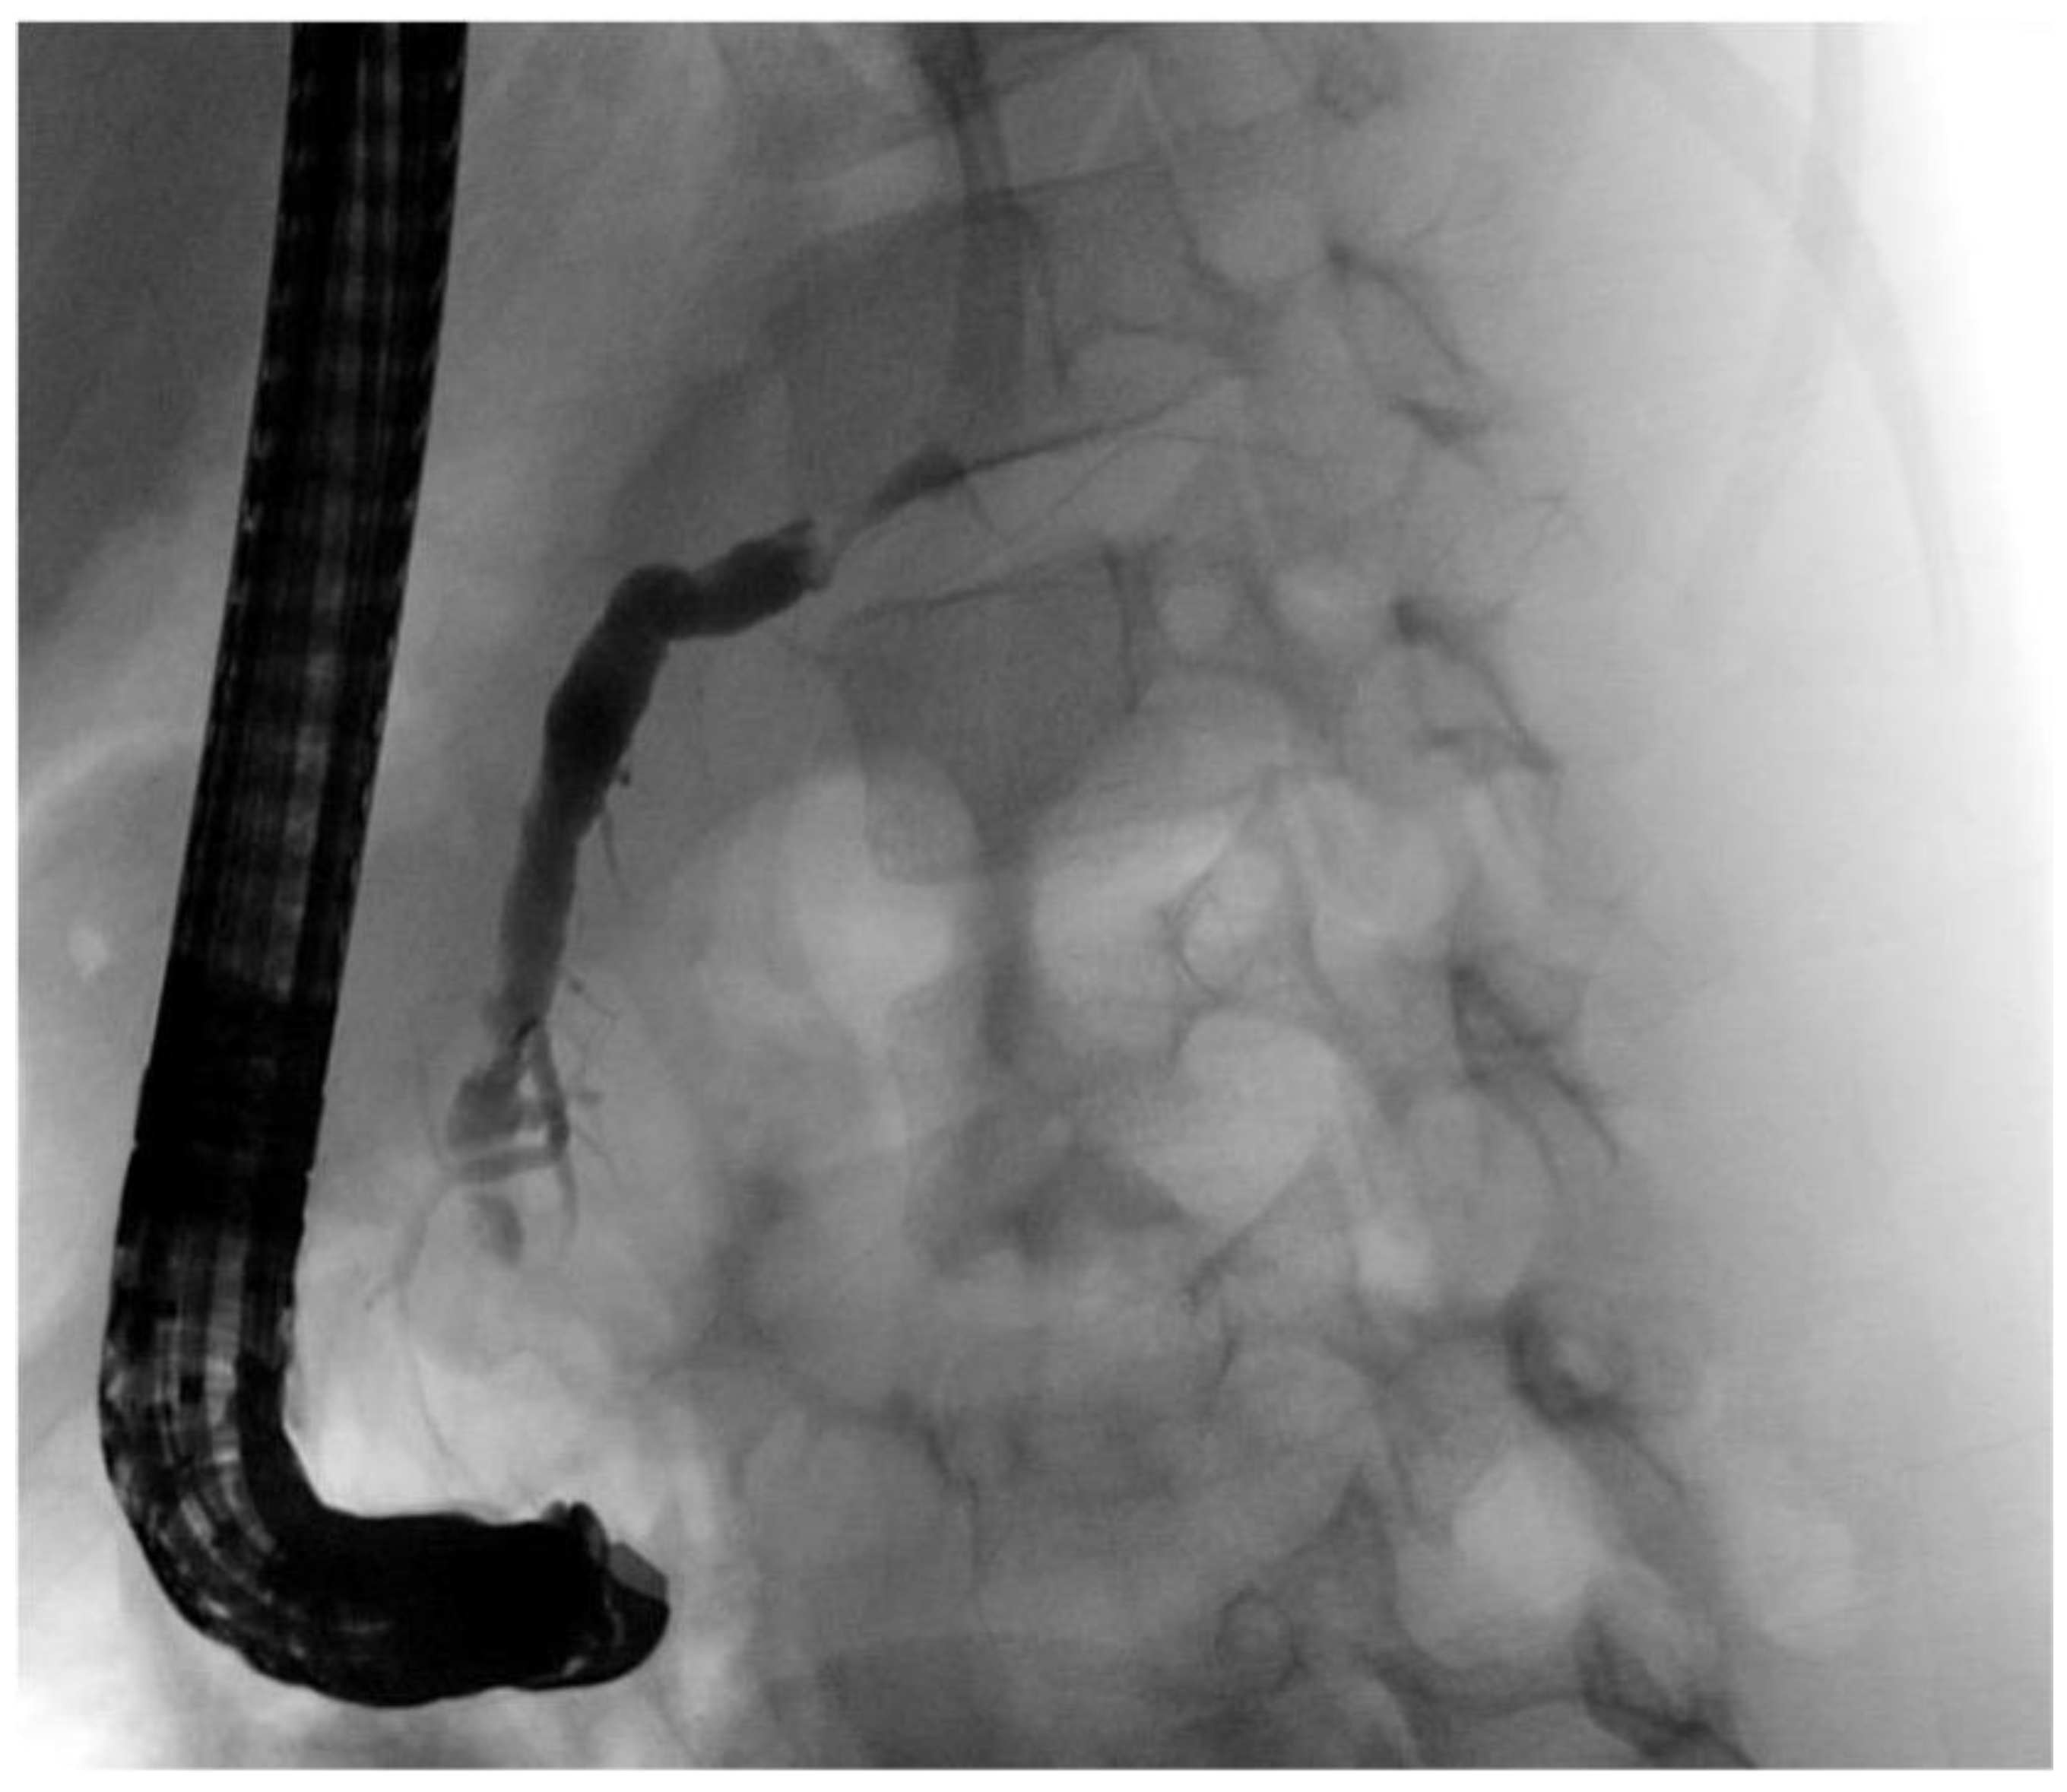

| Initial Management | Laparotomy, suture of the pancreatic head, distal pancreato-jejunostomy (Roux Y) | ERCP—complete dissection of the pancreas, Laparotomy, Jejunal repair, suture of the pancreatic head, distal pancreato-gastrostomy | ERCP—stenting of the ruptured pancreatic duct with 5 Ch pigtail drainage | ERCP unsuccessful, stenting of ruptured pancreatic duct not possible; chest drain (left side) |

| Management of complications | Anticoagulant therapy | - | Transgastric punction and drainage of pseudocyst with double-pig tail drain Ch 7, spontaneous dislocation of pig tail Antibiotic therapy Persistent fistula of the ruptured pancreatic duct, recurrent stenting (2 times), removal of stent after 5 months | Transgastric punction and drainage of pseudocyst with double-pig tail Ch 7, spontaneous dislocation of pig tail Antifungal therapy |